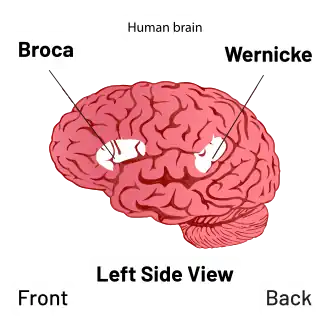

In 1861, Paul Broca reported a post mortem study of an aphasic patient who was speechless apart from a single nonsense word: "Tan". Broca showed that an area of the left frontal lobe was damaged. As Tan was unable to produce speech but could still understand it, Broca argued that this area might be specialised for speech production and that language skills might be localized to this cortical area. Broca did a similar study on another patient, Lelong, a few weeks later. Lelong, like Tan, could understand speech but could only repeat the same five words. After examining his brain, Broca noticed that Lelong had a lesion in approximately the same area as his patient Tan. He also noticed that in the more than 25 patients he examined with aphasia, they all had lesions to the left frontal lobe but there was no damage to the right hemisphere of the brain. From this he concluded that the function of speech was probably localized in the inferior frontal gyrus of the left hemisphere of the brain, an area now known as Broca's area.

Karl Wernicke subsequently reported patients with damage further back in the temporal lobe who could speak but were unable to understand what was said to them, providing evidence for two potentially interconnected language centres. These clinical descriptions were integrated into a theory of language organisation by Lichtheim.[4] Subsequently, these models were used and developed to inform Dejerine's account of reading, Liepmann's theory of action and Lissauer's 1890 account of object recognition and Lewandowsky and Stadelmann's 1908 account of calculation.